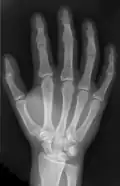

X-ray of the bones in the hand